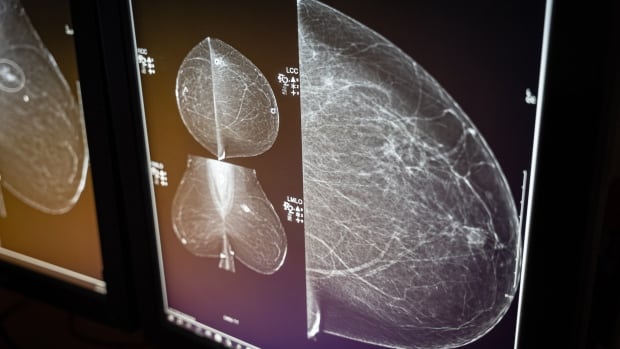

Report warns persistent access issues are putting cancer patients at risk